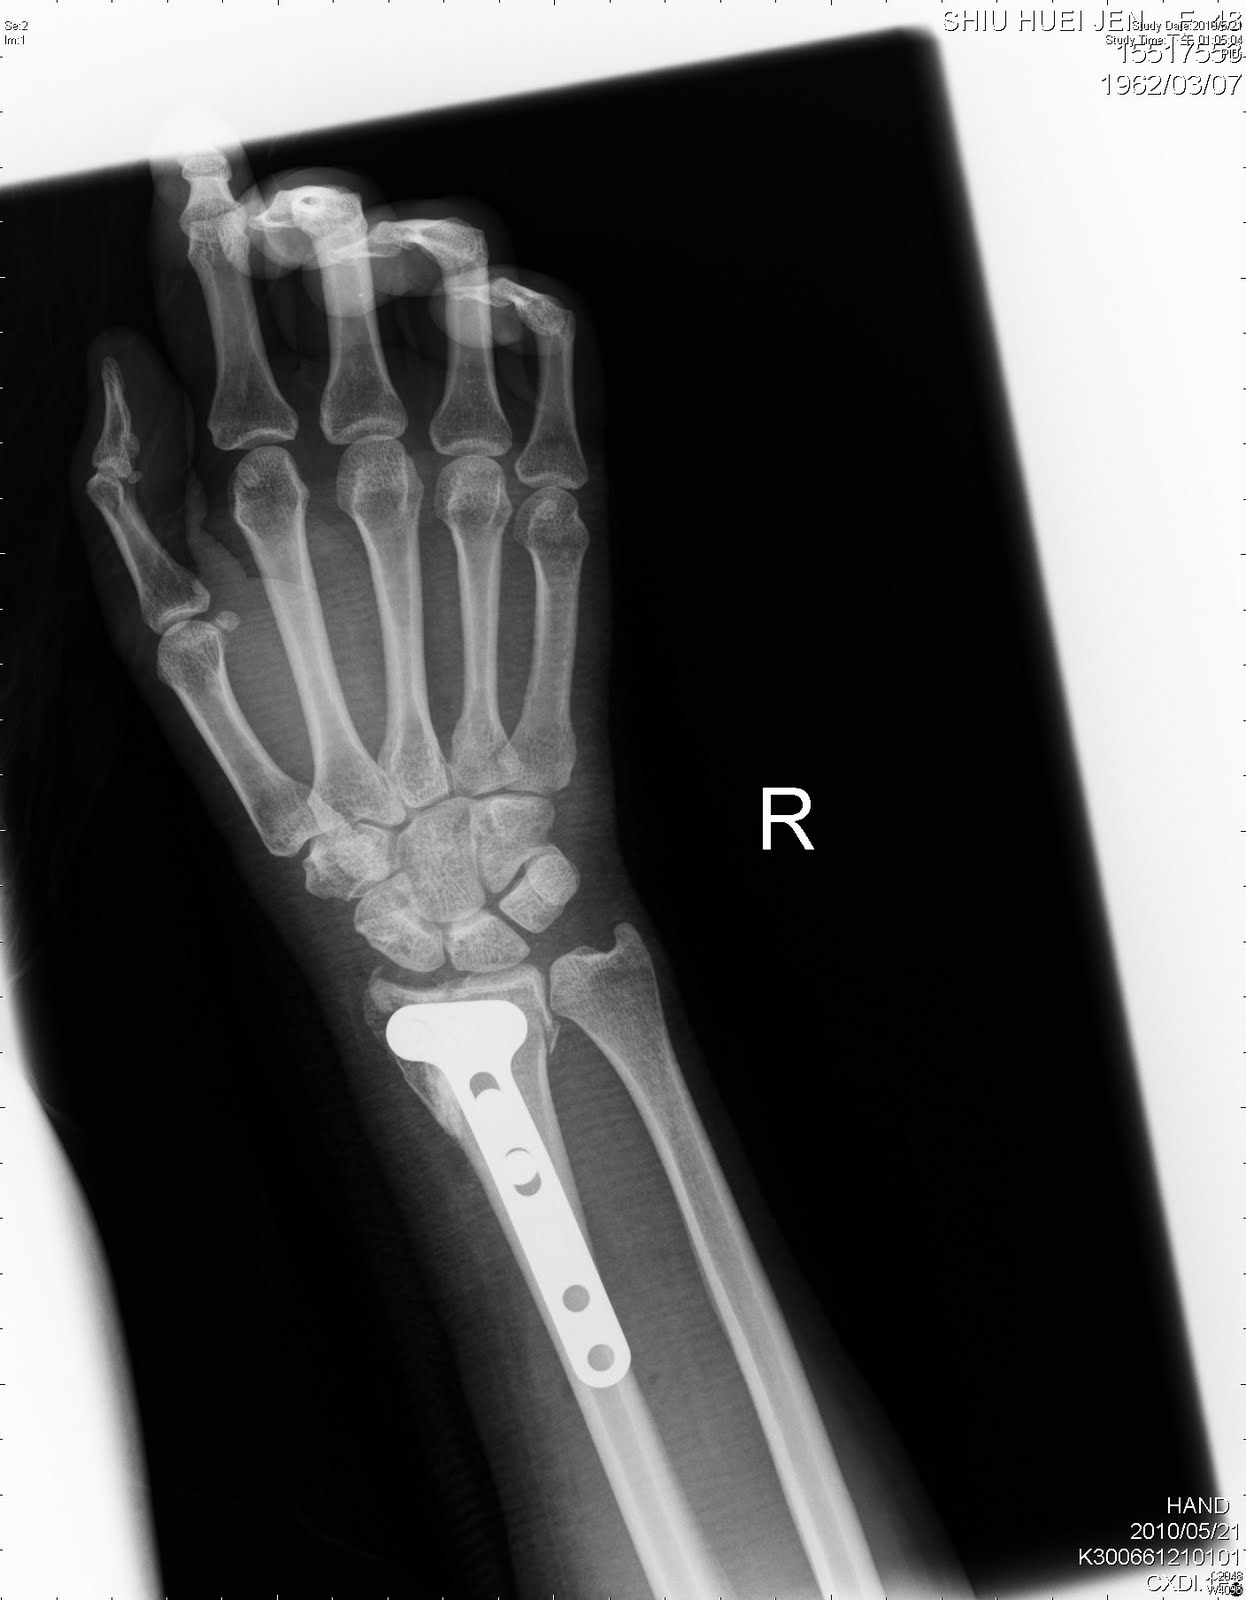

Patients with a suspected fracture of their distal radius will primarily complain of pain, swelling and an inability to use the affected wrist. The appropriate 7th character is to be added to each code from category s62. Icd 10 diagnosis m17.9 gonarthrosis , unspecified m01.56 arthritis in other bacterial disease lower leg m35.4 diffuse fasciitis.

An overview of fractures of the distal radius (wrist fractures) including causes, symptoms, examination, investigations, management and complications. It covers icd codes 800 to 999. The distal ulna articulates with the sigmoid smith's fractures occur in younger patients and are the result of high energy trauma on the volar flexed wrist. Wrist fractures may involve the lower end of one or both of the forearm bones (radius or ulna) or, less often, a bone in the base of the hand. Patients with a suspected fracture of their distal radius will primarily complain of pain, swelling and an inability to use the affected wrist. Wrist fractures may occur when enough force is applied to the wrist, such as when falling down onto an outstretched hand. If the wrist fracture was not treated and was displaced most of the time will heal but in deform way that cause malfunction of the wrist joint and lea. You can always come back for icd code for wrist fracture because we update all the latest coupons and special deals weekly. A patient experienced a closed head injury. The fracture was treated with a closed reduction procedure. You can get the best discount of up to 50% off. To code a diagnosis of this type, you must use one of the three child codes of s62.9 that describes the diagnosis 'unspecified fracture of wrist and hand' in more detail. Wrist pain can come from a wide range of causes, this could be a old fracture, or broken bone, arthritis, or those individuals that play lots of sports that involve alot of hand movements. Icd 10 diagnosis m17.9 gonarthrosis , unspecified m01.56 arthritis in other bacterial disease lower leg m35.4 diffuse fasciitis. 814.12 open fracture of lunate semilunar bone of wrist. Care guide for wrist fracture in adults. An overview of fractures of the distal radius (wrist fractures) including causes, symptoms, examination, investigations, management and complications.